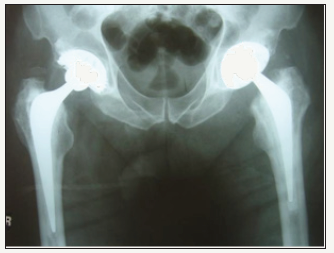

A 67 year old female underwent right total hip arthroplasty for osteoarthritis (Figure 11). A 56mm Pinnacle sector 2 acetabular cup with a neutral Marathon polyethylene liner (28mm IDx56mm OD) was mated via a 28mm+3 stainless steel Elite femoral head (9/10 taper) to a cemented No 2 high offset C-Stem (9/10 taper) femoral component. Post-op recovery was uneventful and X-Rays showed 46° inclination of the cup (Figure 12).

figure 11: Pre-op film showing right hip osteoarthritis.

figure 12: Post-op film showing right total hip arthroplasty.

figure 13: Right hip disassociation.

figure 14: Lateral film of disassociation.

At six week follow-up she was mobilising well, with good range of movement of the hip and no complaints of pain. At six months post-op she was seen acutely after feeling a pop in her hip following flexing forwards. She complained of pain in her groin and was noted to be walking with a limp. X-Rays showed an eccentrically placed femoral head (Figure 13 & 14).

She proceeded for revision. Again the three superiorly placed locking tabs of the six had sheared off resulting in the liner lying loose. Cup and femoral anteversion were deemed acceptable and there was no evidence of loosening. The disassociated liner was replaced with a neutral metal Pinnacle liner (36mm IDx56mm OD) and the femoral head component with a 36mm+3 offset stainless steel Ultamet femoral head (9/10 cone). Post-op recovery was uneventful and on review in outpatient clinic both at six weeks and two years post-op she remained well with full range of movement of the hip and no further instability (Figure 15).

figure 15: Post-revision.